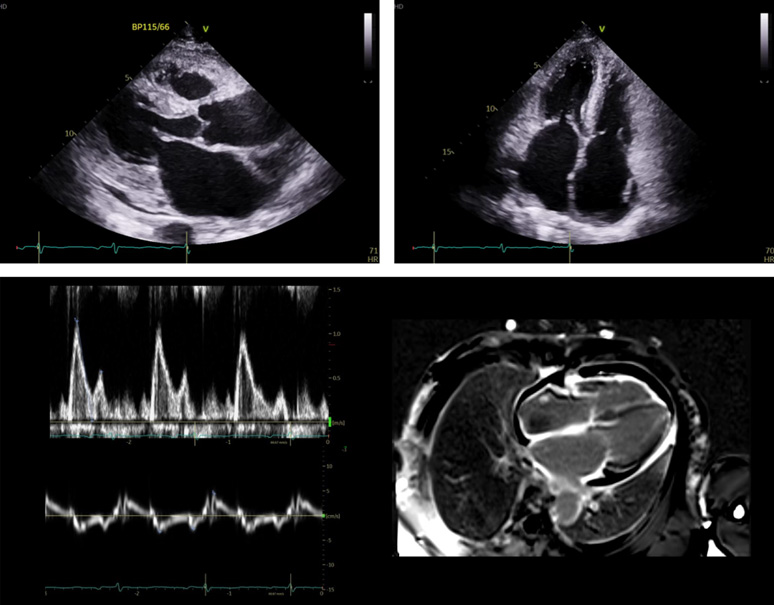

심초음파검사상 left ventricle과 right ventricle에 diffuse한 wall thickening과 함께 bi-atrial enlargement가 저명하며 mitral inflow와 tissue Doppler상 restrictive pattern이 관찰되어 amyloidosis에 의한 restrictive cardiomyopathy가 의심된다.

심장 MRI검사의 Late gadolinium enhancement가 LA, RA, RV에 diffuse하게 관찰되며, T1값이 1417.6 ms로 상승되어 있으며 ECV fraction 48.1% 로 증가되어 있다.